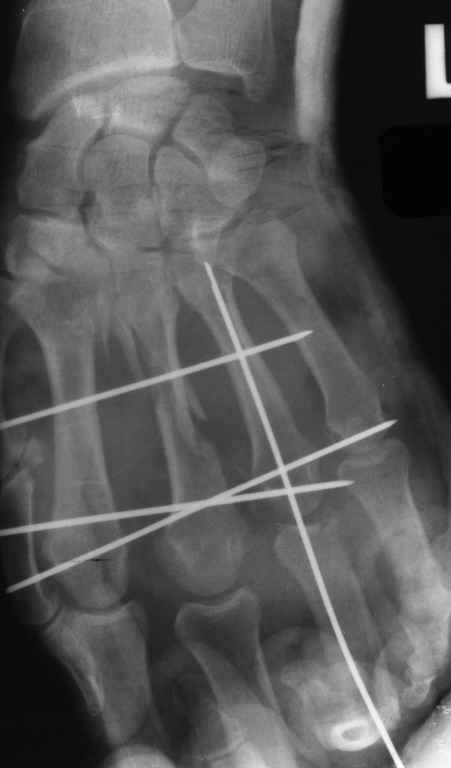

Диагноз на 15.07.05: Стойкая смешанная дермотеногенная контрактура 3,4 пальца правой кисти 3 степени.

-- удалить спицы;

-- сделать рентгенограмму;

Диагноз: Стойкая Смешанная дермотеногенная контрактура 3,4 пальца правой кисти.

Судя по выписному эпикризу, рентгенограммам и фотографиям, пациенту

показано этапное лечение.

Зачем спица в 4 Пястной кости?